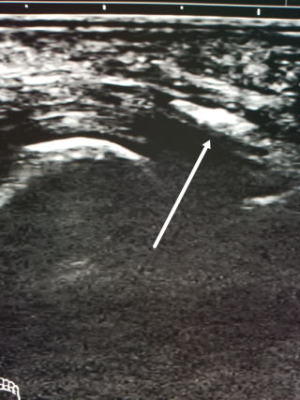

蹴りを大腿に受けて受傷。正座をすると突っ張るとのことで来院。触診で大腿前面の腫れと皮下の硬結を認める。レントゲンでは骨傷なし。超音波では中間広筋内部に高エコーの石灰化を思わせる像を認めました。

*石灰化はレントゲンより超音波の方が遙かに感度が高いです。

レントゲンで大腿骨前面に石灰化を認めます。超音波では石灰化が成長してくっきりと見えています。